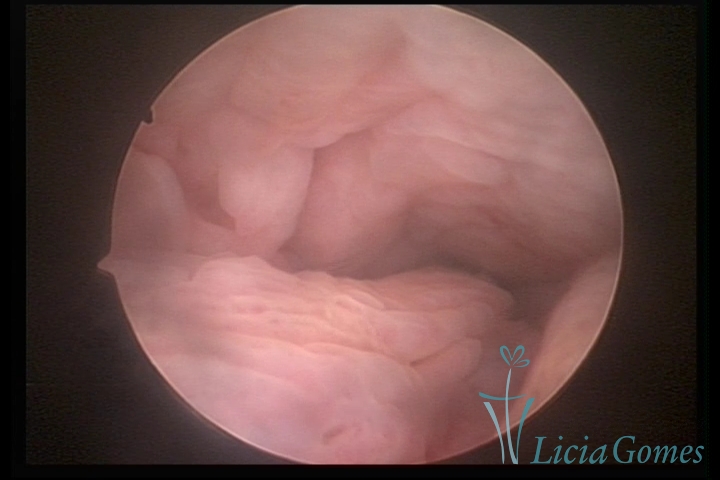

Terceira porção ou porção superior

Apresenta a mucosa com a superfície lisa e pouco vascularizada até a altura do orifício interno